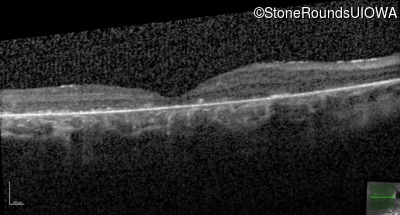

Age at visit: 8 years

This 8 year old girl had normal vision until age 6 when she failed a school vision screening. That year, she was able to play softball well, but this year she often loses sight of the ball and is often hit by it.